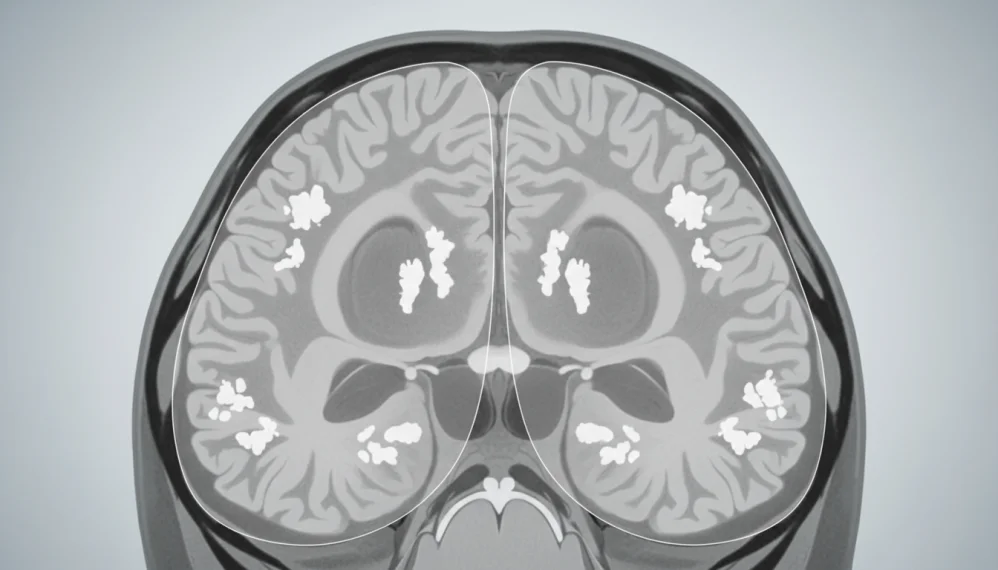

Sindromul Fahr reprezinta o boala neurodegenerativa destul de rara in populatie ce se caracterizeaza prin prezenta unor depozite de calciu (zone de calcifiere) in diverse regiuni cerebrale, de exemplu in ganglionii bazali, ce determina afectarea celulelor din aceasta zona si in final moartea lor.

Datorita faptului ca nu exista o cauza identificata pentru aparitia acestei boli, specialistii au numit-o si "calcificare idiopatica a ganglionilor bazali". Zonele afectate, in principal ganglionii bazali si cortexul cerebral, sunt implicate in controlul miscarii.